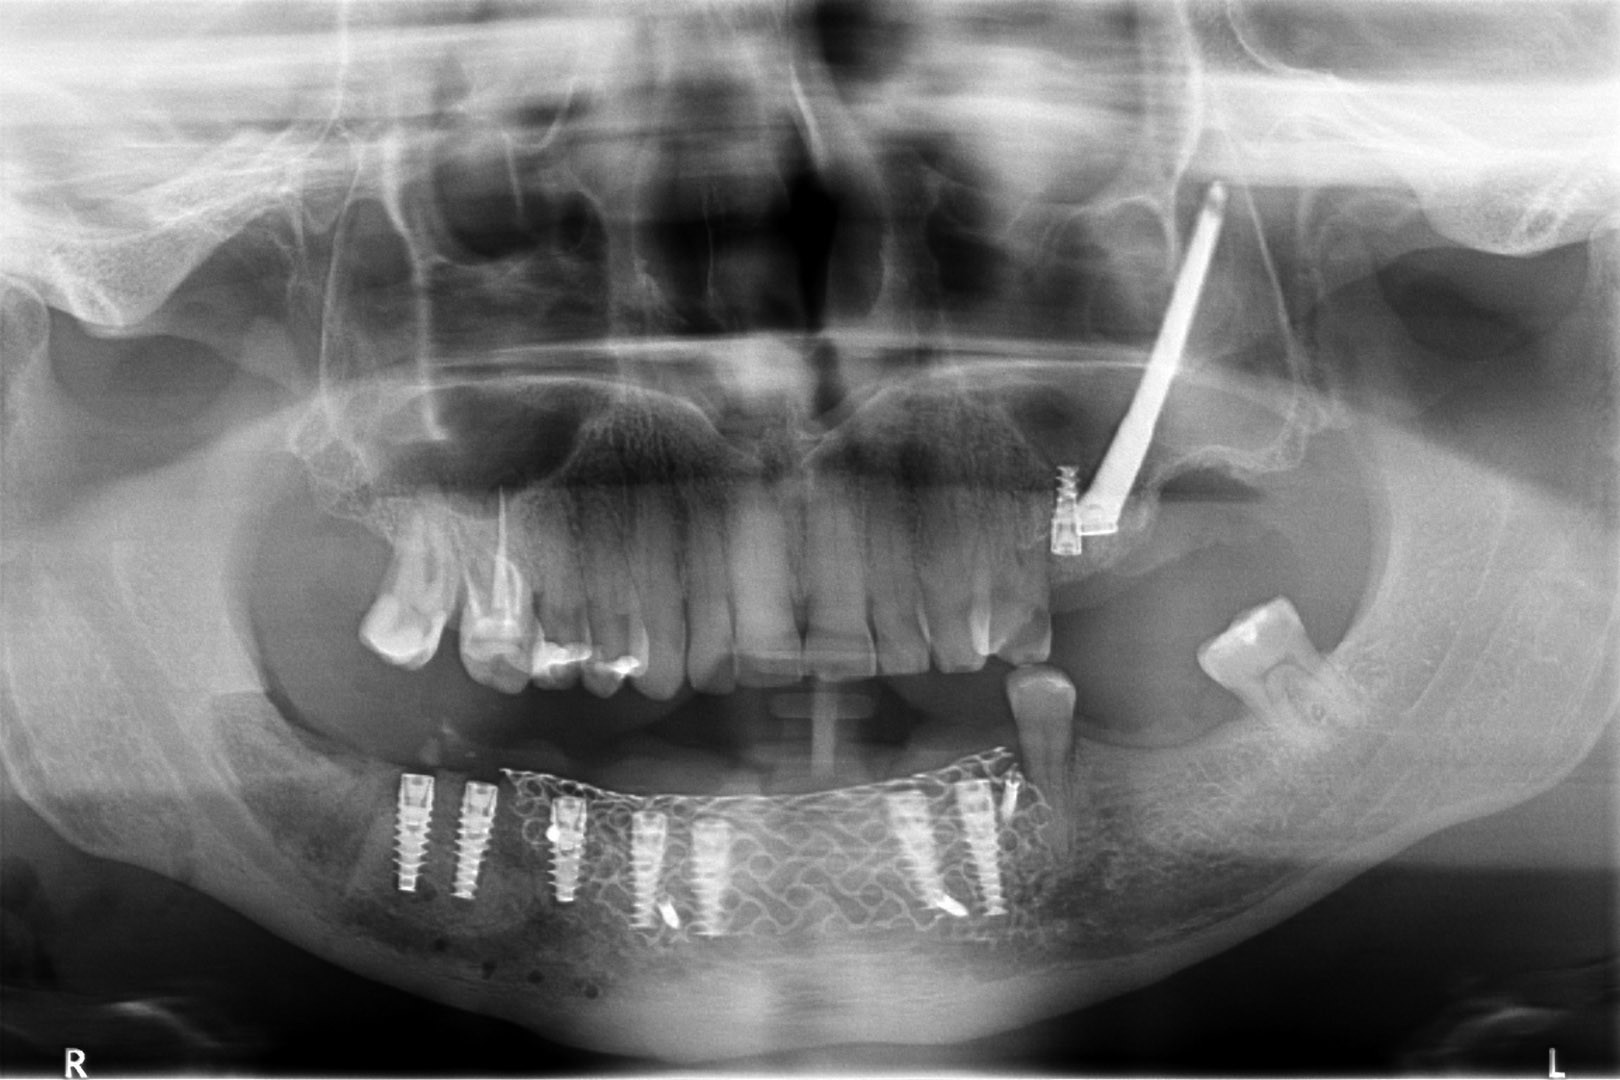

Ta szczególna metoda używana jest w obszarze dolnego łuku zębowego w sytuacji braku dostatecznej ilości kości na wysokość. Metoda stosowana jest w sytuacji rozległych zaników kostnych w bocznych odcinkach żuchwy, w której wprowadzenie implantów groziłoby uszkodzeniem gałązek nerwowych nerwów zębodołowych dolnych. Gałązki nerwowe biegną wraz z naczyniami krwionośnymi we wspólnej pochewce w kanałach kostnych, umieszczonych symetrycznie po obu stronach w trzonach żuchwy.

Technika polega na chirurgicznym ich przemieszczeniu, a przez to stworzeniu bezpiecznego miejsca dla wszczepienia implantów o odpowiednej długości, co gwarantuje ich stabilną pozycję. Stosuje się ją wraz z zabiegiem rekonstrukcji kostnej przy użyciu biomateriałów w formie granulatu i membran. Zabieg ten stosowany jest rzadko, jako alternatywa rozległych regeneracji kostnych. Wybierany bywa jako alternatywa operacyjna tylko w sytuacji, gdy konwencjonalne metody odbudowy kostnej są niewystarczające lub generują ryzyko braku skutecznej odbudowy kostnej celem wszczepienia implantu.

Nasza klinika szczyci się tym, że dr Witkowski opracował własną technikę zabiegu transpozycji nerwów zębodołowych, która prezentowana była na Konferencji Towarzystwa Piezosurgery we Florencji w 2013 roku.

To kolejna metoda umożliwiająca precyzyjną odbudowę zadanego kształtu tkanki kostnej przy użyciu standardowych materiałów kościotwórczych, kości własnej lub PRF oraz zewnętrznego rusztowania w postaci siatki z biozgodnego stopu tytanu. Siatka jest indywidualnie projektowana w technologii CAD CAM i następnie drukowana dla konkretnego przypadku.

Dotychczas stosowane stabilizatory zewnętrzne w formie siatek tytanowych używane do regeneracji kostnej lub w zabiegach odtwórczych w chirurgii szczękowo-twarzowej uwzględniały materiały ręcznie doginane i formowane podczas zabiegu operacyjnego. Zastosowanie technologii CAD CAM dla potrzeb druku materiałów przeznaczonych do indywidualnej rekonstrukcji kostnej znacznie poprawiło precyzję i jakość uzyskiwanych efektów. Wdrożenie biozgodnych stopów tytanu do druku siatek zdecydowanie ograniczyło odsetek powikłań zapalnych.

Siatki stanowią stabilną obudowę – ograniczenie nadające kształt regenerowanej kości przy użyciu upakowanego pod nią materiału. Utrzymują i stabilizują rozdrobniony granulat kościotwórczy, co jest warunkiem prawidłowego procesu gojenia, jednocześnie nadając anatomiczny kształt i zakres odbudowie kostnej sprzed jej zaniku.

Precyzja projektu druku siatki bazuje na dokładności odwzorowania kształtu kości w stożkowej tomografii komputerowej CBCT, co zapewnia ich dobre przyleganie do podłoża kostnego oraz ogranicza powstawanie powikłań w postaci obnażania się siatek.

Precyzja projektu oraz materiał, z którego wykonana jest siatka (biozgodny stop tytanu), powodują, że obnażenie się siatki nie zaburza procesu gojenia i regeneracji kostnej. Wymaga jedynie większej ilości kontroli pozabiegowych oraz wzmaga czujność higieniczną zarówno ze strony lekarza, jak i pacjenta.

Ten rodzaj odbudowy kostnej stosowany jest w sytuacjach złożonych, trójwymiarowych 3D ubytków kości, przy których standardowe metody odbudowy są niewystarczające. Ilość kości, którą możemy uzyskać, stosując tę metodę, to nawet kilka centymetrów sześciennych.

Metoda rekonstrukcji kostnej w oparciu o indywidualnie drukowane siatki z tytanu dla implantacji wszczepów śródkostnych stosowana jest najczęściej jako dwuetapowa. W pierwszym etapie odbudowywana jest kość, natomiast implanty wszczepiane są po okresie 4–6 miesięcy. Na wgojenie implantów oczekujemy od 4 do 6 miesięcy w zależności od miejsca ich lokalizacji. Siatka tytanowa po spełnieniu swojej funkcji rusztowania dla odbudowującej się kości jest następnie usuwana w dniu wszczepienia implantu. Jeżeli kość spełnia odpowiednie warunki, istnieje możliwość zastosowania modyfikacji siatki tytanowej, która umożliwia jednoczesne wprowadzenie implantów wraz z odbudową kostną. Wariant ten skraca czas od pierwszego zabiegu do wykonania gotowych koron protetycznych na wprowadzonych implantach.